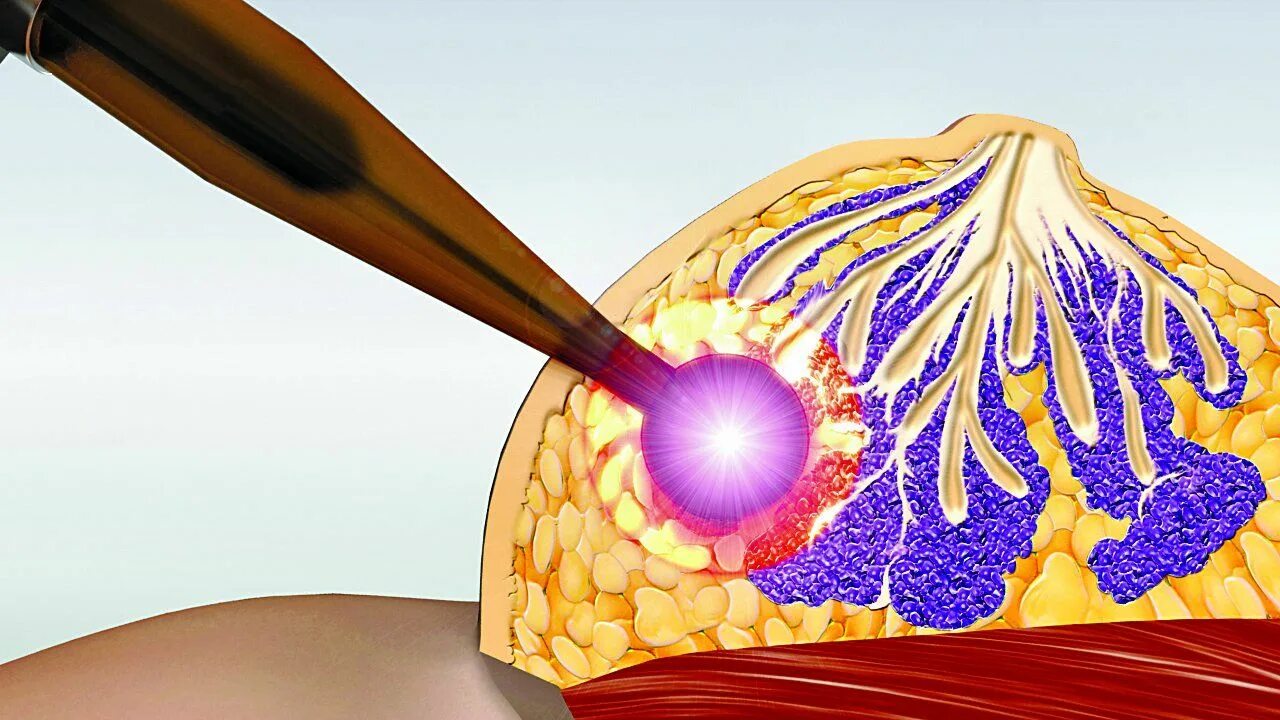

Лучевая терапия метастазов в лимфоузлах